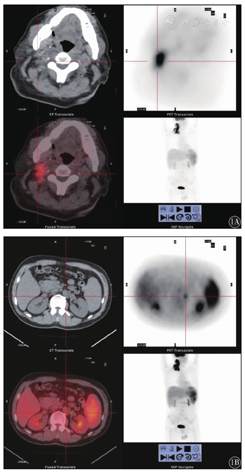

136例淋巴瘤患者中,18F-FDG PET-CT检测阳性111例,增强CT检测阳性96例,两种方法诊断结果与病理诊断结果比较见表1。18F-FDG PET-CT诊断的灵敏度、特异度、准确率、阳性预测值、阴性预测值分别为92.8%、82.1%、94.9%、95.5%、92.0%,而增强CT诊断则分别为80.6%、67.9%、77.9%、90.6%、47.5%。两种方法诊断的灵敏度及特异度差异有统计学意义(χ2=16.0,P<0.01),进一步分析显示,18F-FDG PET-CT的灵敏度高于增强CT(χ2=17.1,P<0.01),而两种检查方法的特异度差异无统计学意义(χ2=2.3,P=0.130)。18F-FDG PET-CT诊断淋巴瘤的准确率高于增强CT。Kappa一致性检验显示,18F-FDG PET-CT和增强CT诊断结果一致性较好(κ=0.543,P<0.01)。18F-FDG PET-CT和增强CT共同诊断阳性患者所占比例为67.6%(92/136),病理结果证实,94.6%(87/92)为真阳性,5.4%(5/92)为假阳性。18F-FDG PET-CT阳性而增强CT阴性患者所占比例为14.0%(19/136),病理结果证实,此19例均为真阳性。18F-FDG PET-CT阴性而增强CT阳性患者所占比例为2.9%(4/136),病理结果证实,此4例均为真阴性。18F-FDG PET-CT和增强CT均阴性患者所占比例为15.4%(21/136),病理结果证实,90.5%(19/21)为真阴性,二种方法共同漏诊率为9.5%(2/21)。典型病例:1例患者因不明原因发热行18F-FDG PET-CT检查,提示颈部、锁骨下、腹膜后区主动脉旁多发肿大淋巴结,FDG代谢增高,最大标准摄取值(SUVmax)11.6,脾明显增大,FDG代谢异常增高,SUVmax 4.0;常规CT图像不能判断是否为恶性增生;行18F-FDG PET-CT后,发现全身多发淋巴结肿大伴代谢增高,诊断为淋巴瘤;最终病理活组织检查证实为HL(图1)。